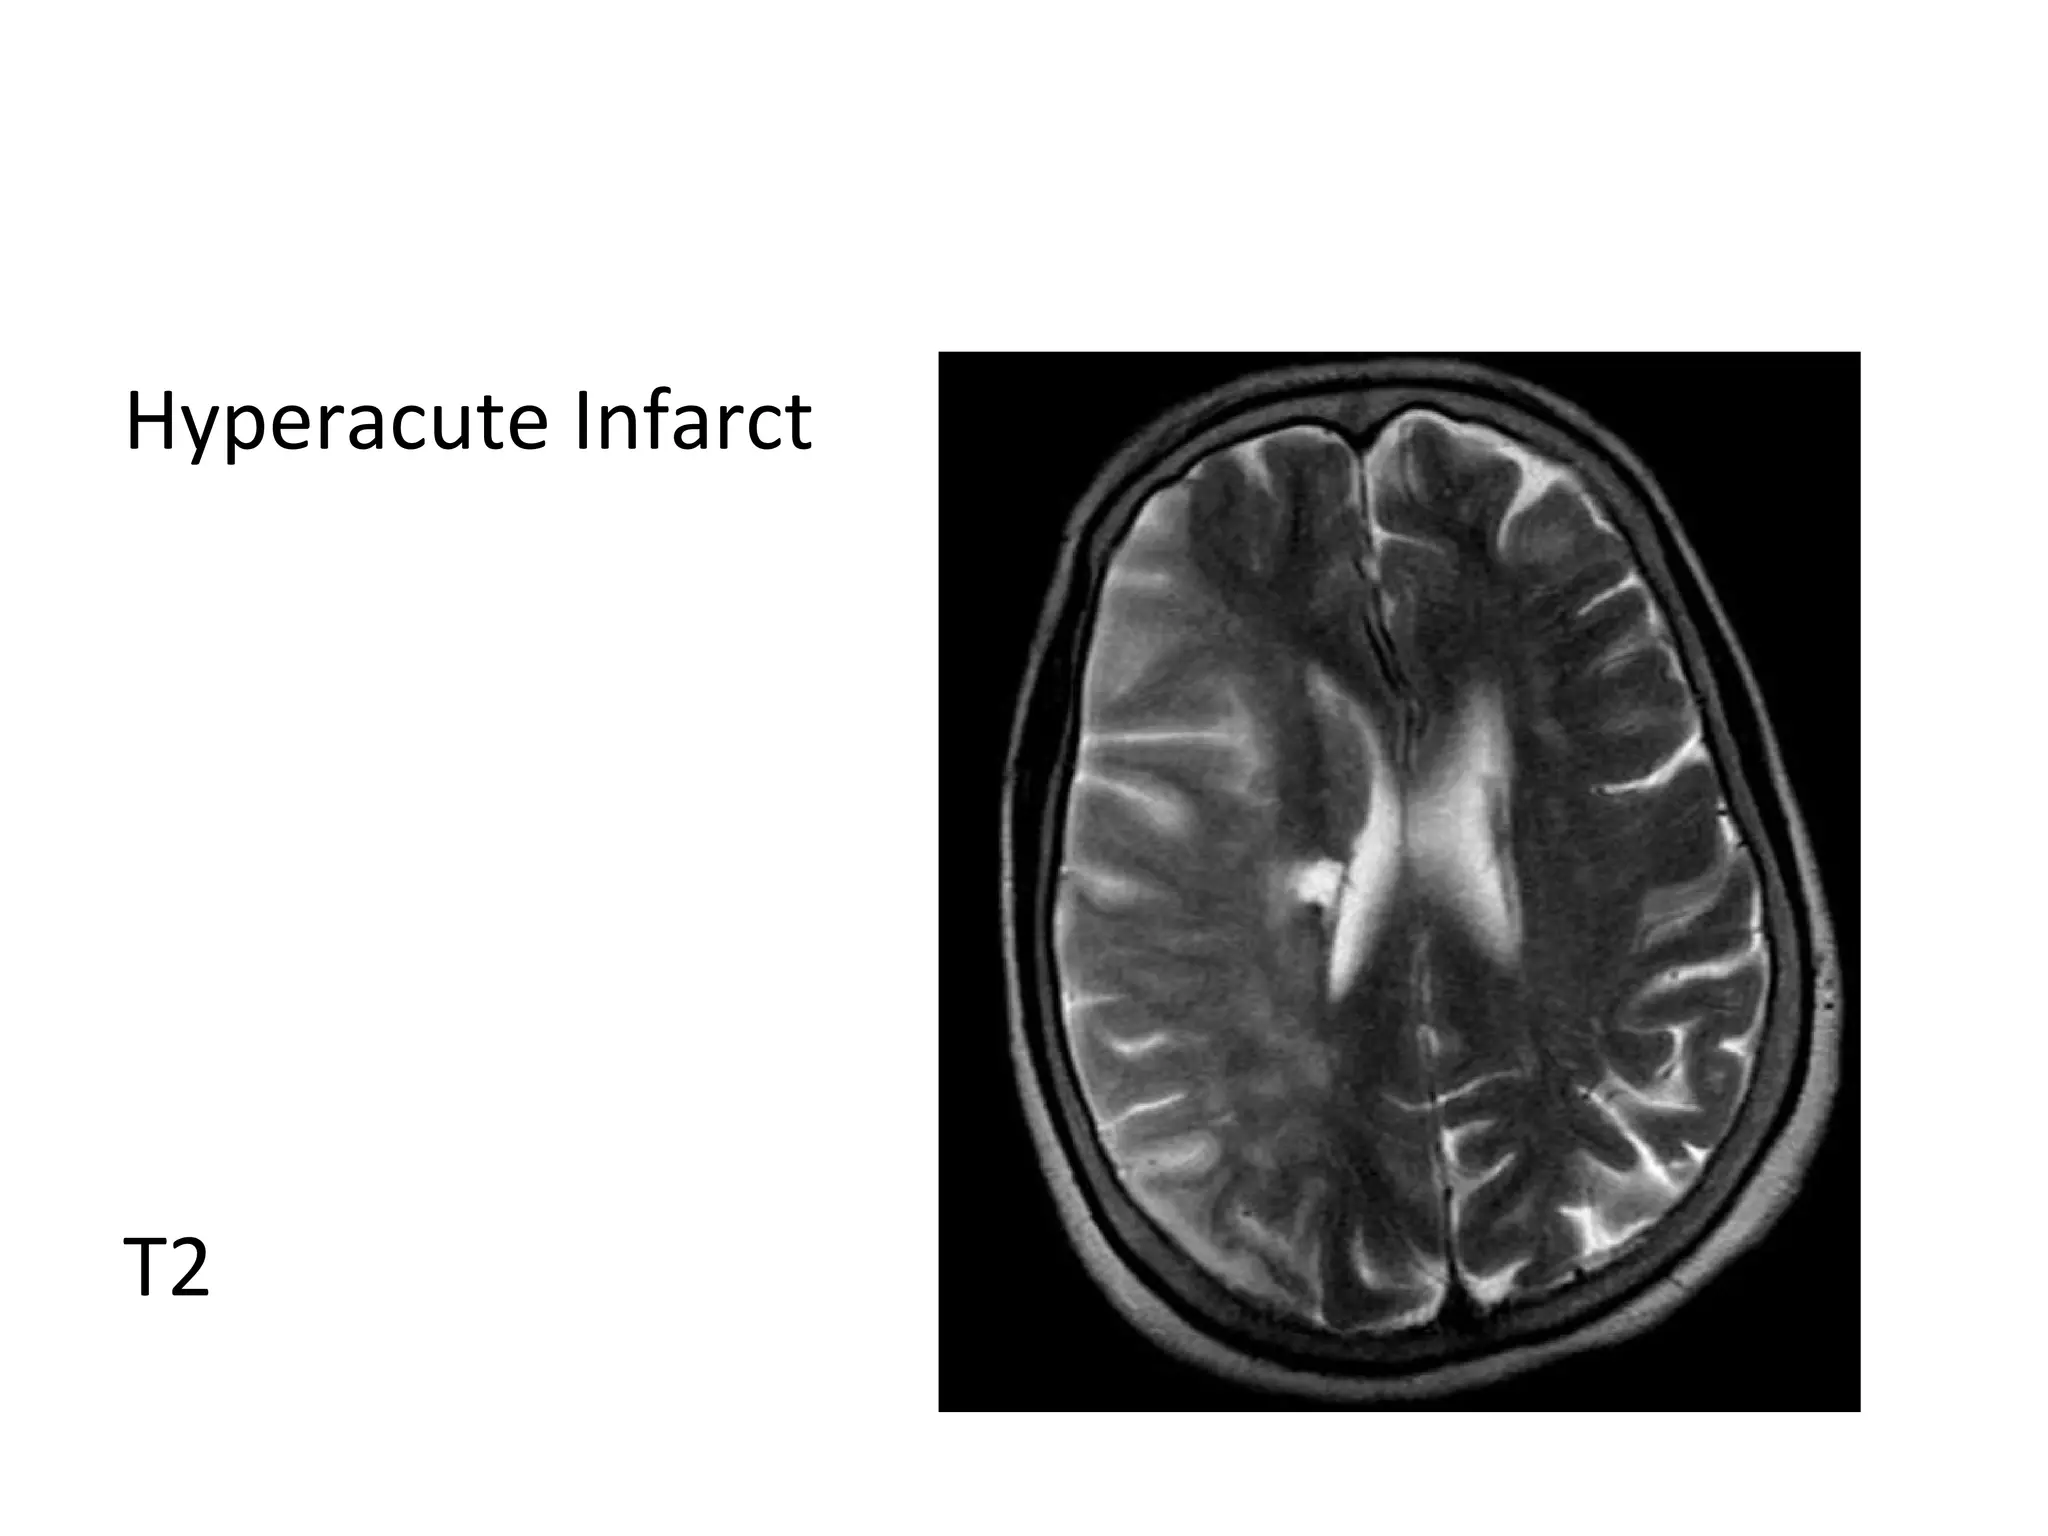

Hyperacute Infarct

T2

a) Hyperacute Infarct (0-6 hours) :

-FLAIR may be normal , subtle hyperintensity may be

seen on FLAIR